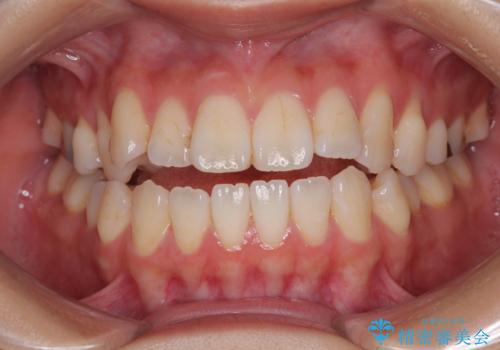

最新の症例

Latest cases